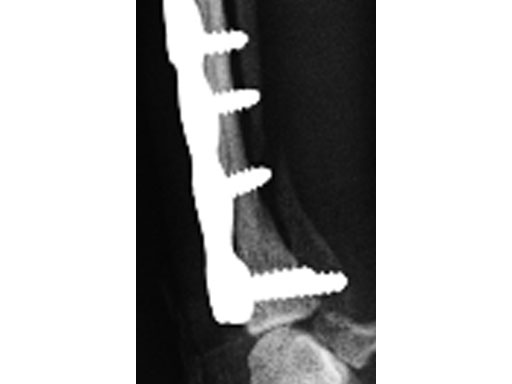

The dog was discharged from the hospital 2 days postoperatively with instructions for strict exercise restriction; the dog was ambulatory on all four limbs at this time, although lame on the right forelimb. The bandage was to be removed in about 57 days. The dog did very well and was reevaluated 8 weeks postoperatively, at which time radiographs revealed a healed radius and atrophic ulna (Fig 4 - the ulnar atrophy is the norm in the canine for this repair in these small dog breeds). The dog was fully ambulatory and without lameness at this time; however, there was a slight decrease in full flexion at the antebrachiocarpal jointagain, this is the norm with this repair due to the surgical dissection and plate placement under the extensor tendons, which does not cause any functional deficit in the dog. The dog was gradually returned to full activity over the ensuing 2 weeks. It is recommended that these dogs not be allowed to jump from heights (eg, bed, chair) as they are at increased risk for this fracture, regarding the opposite limb in this patient.